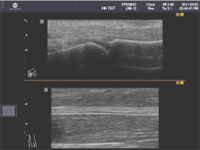

3.上下2画面表示機能搭載

上下に2画面表示する機能が搭載され、疾患部位と健常部位の画像を上下に表示することで、横に広い検査画像を比較することが可能です。この機能により、整形外科などでも大変使い易くなりました。